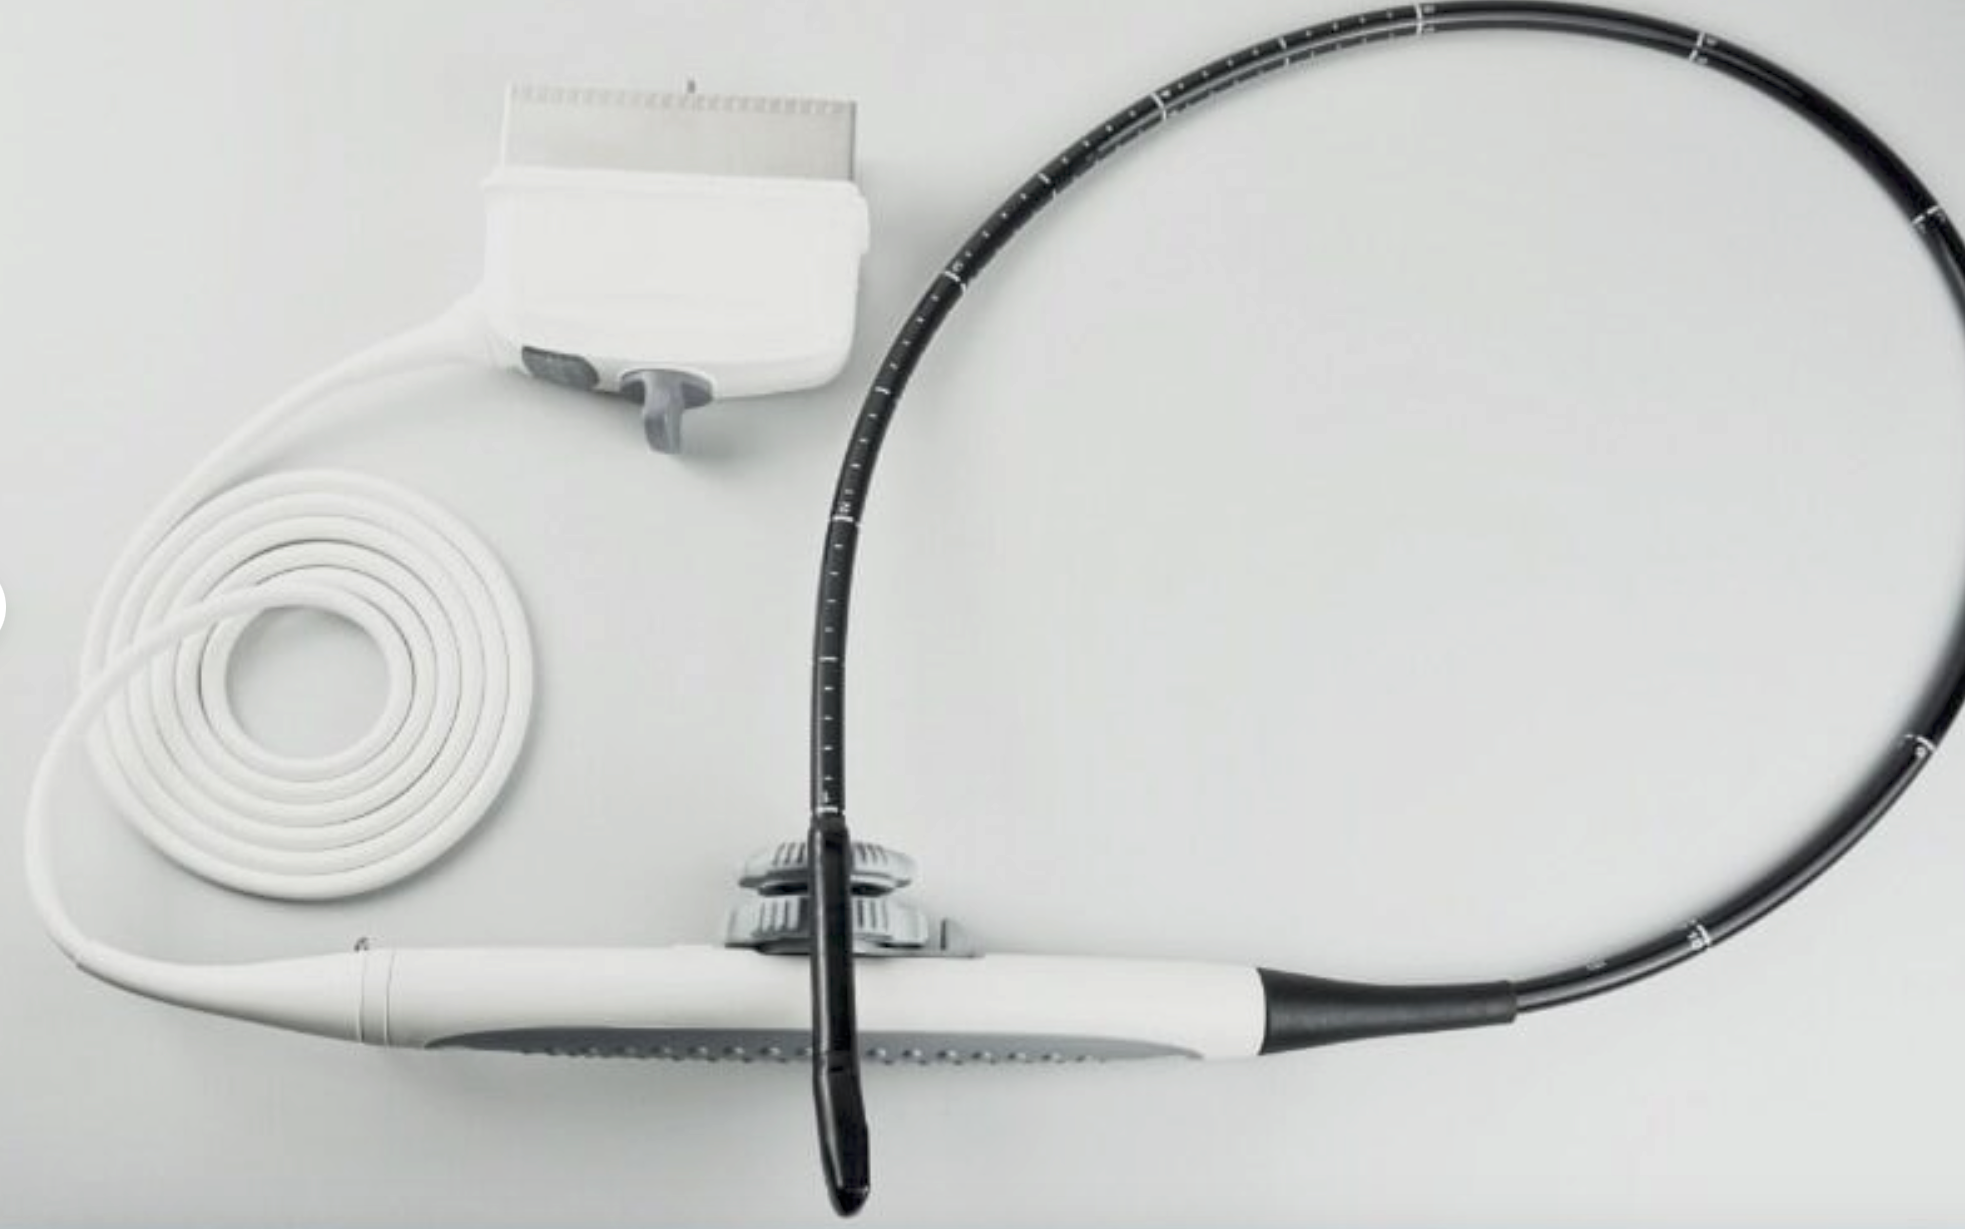

DIAGNOSTIC ULTRASOUND MACHINES FOR SALE

DIAGNOSTIC ULTRASOUND MACHINES FOR SALE

Philips iU22 - A Cart, 3D/4D Ultrasound

Sale price$ 21,585.66